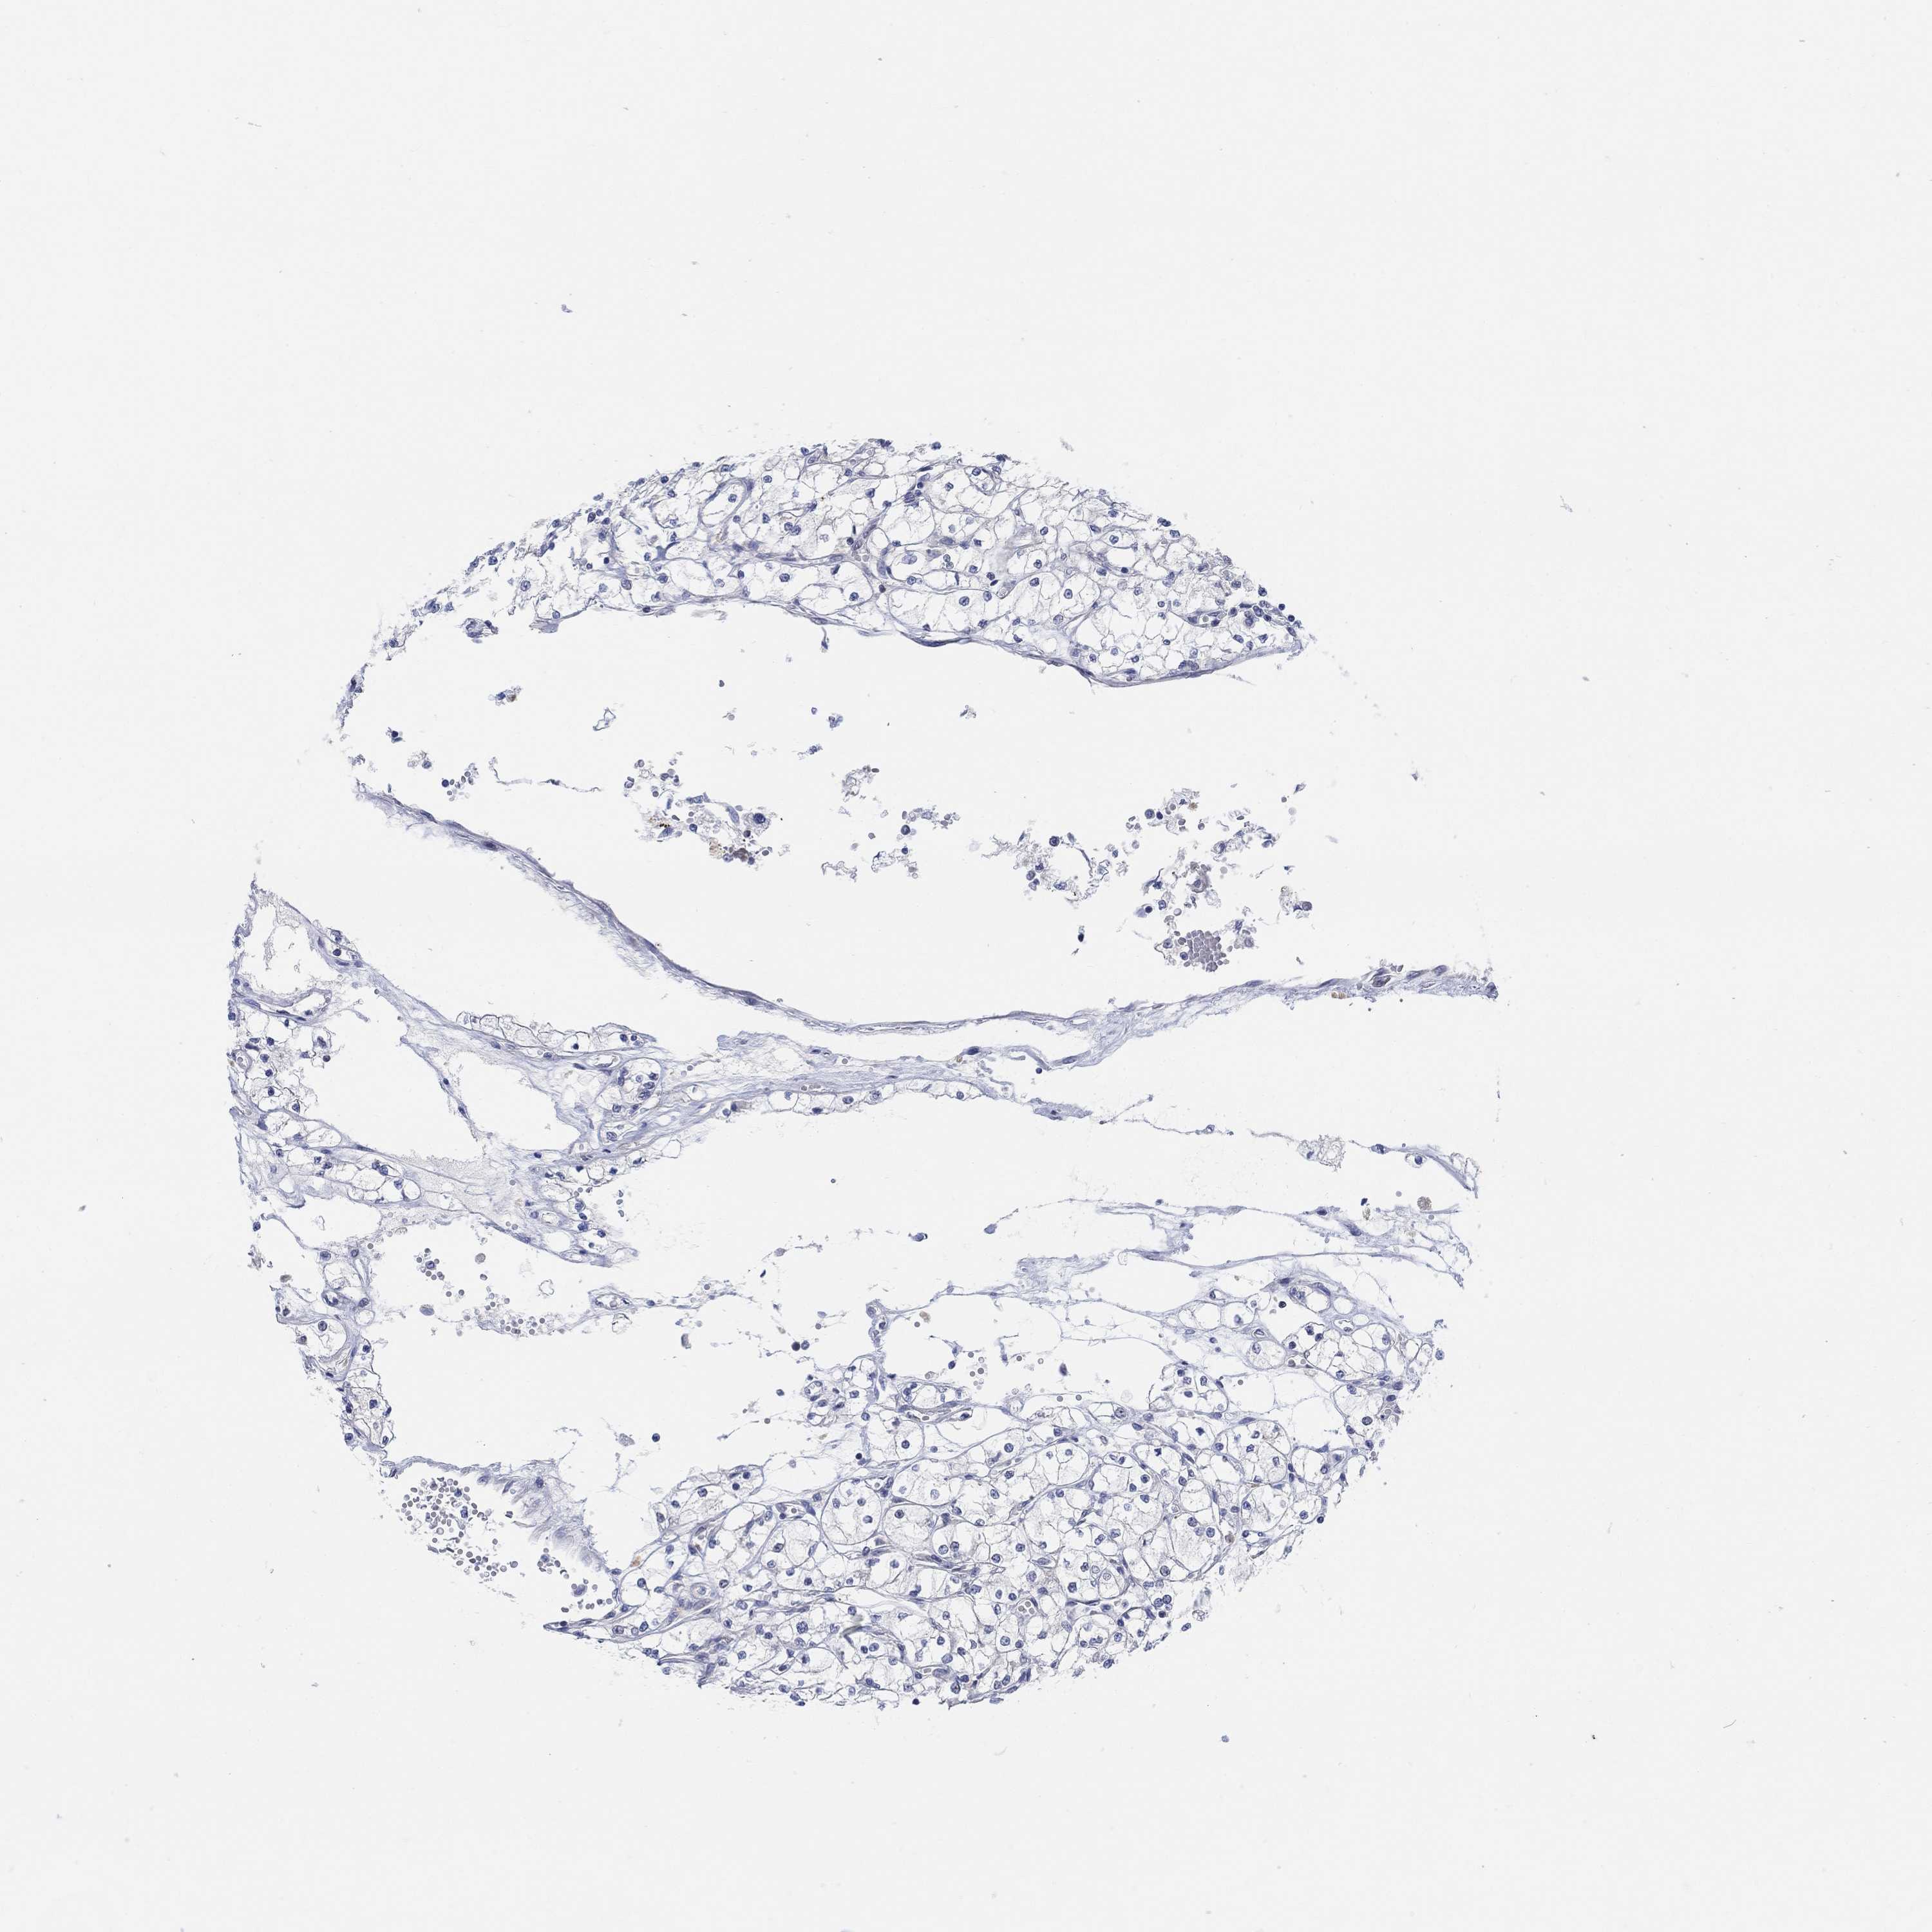

KIDNEY RENAL CLEAR CELL CARCINOMA (VALIDATION) - Interactive survival scatter ploti

The Survival Scatter plot shows the clinical status (i.e. dead or alive) for all individuals in the patient cohort, based on the same data that underlies the corresponding Kaplan-Meier plots. Patients that are alive at last time for follow-up are shown in blue and patients who have died during the study are shown in red.

CNTF is not prognostic in Kidney Renal Clear Cell Carcinoma (validation)